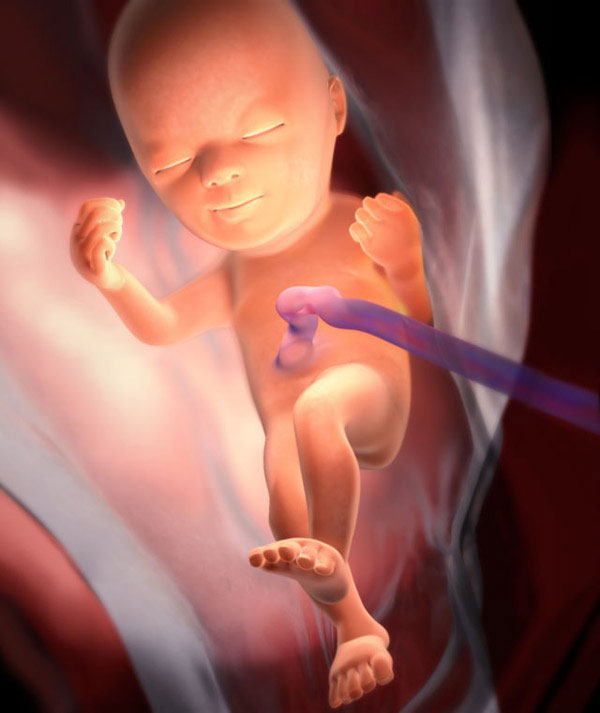

Les proportions du corps fœtal sont près de 100% proches des paramètres du nouveau-né. La seule différence est que le bébé a l'air mince, avec des bras et des jambes très fins et une peau ridée. En effet, la couche de graisse sous-cutanée n'est pas complètement formée.

Voici à quoi ressemble le fœtus à 24 semaines:

Toujours en cours:

- minéralisation osseuse;

- la formation de gyrus cérébral;

- mouvements réflexes (déglutition, respiration, mouvements);

- un cœur développé compte environ 140-160 battements par minute.